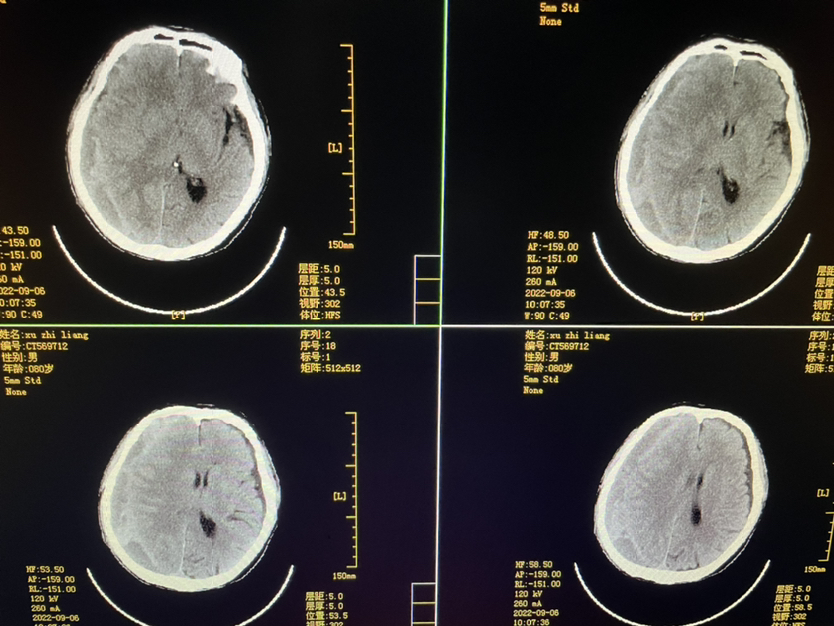

明确外伤史二月,80y,